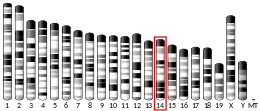

It is associated with Charcot–Marie–Tooth disease 1F and 2E.[5]